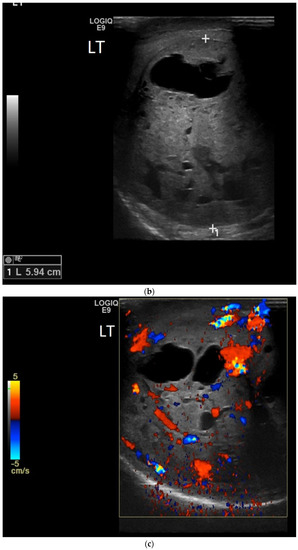

4.4. Teratoma

| Teratomas | Complex mass with well-defined borders Predominately cystic but can also contain macroscopic fat and calcifications |